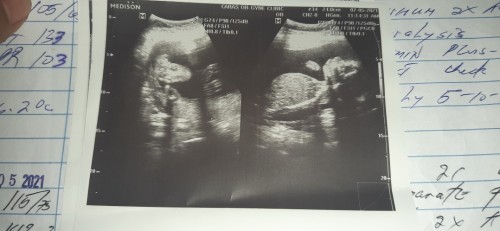

1st time mom here 🥰 Ask ko lang po sana mga mamsh pang 37 weeks ko ngayon at may red/pink na discharge sakin at after nun e may paunti unting watery na may sipon na lumalabas sakin . Walang kahit anong pain po ako nararamdaman . Ano po kaya ibig sabihin non . Normal lang po ba yon. #pleasehelp #advicepls #1stimemom #pleasehelp